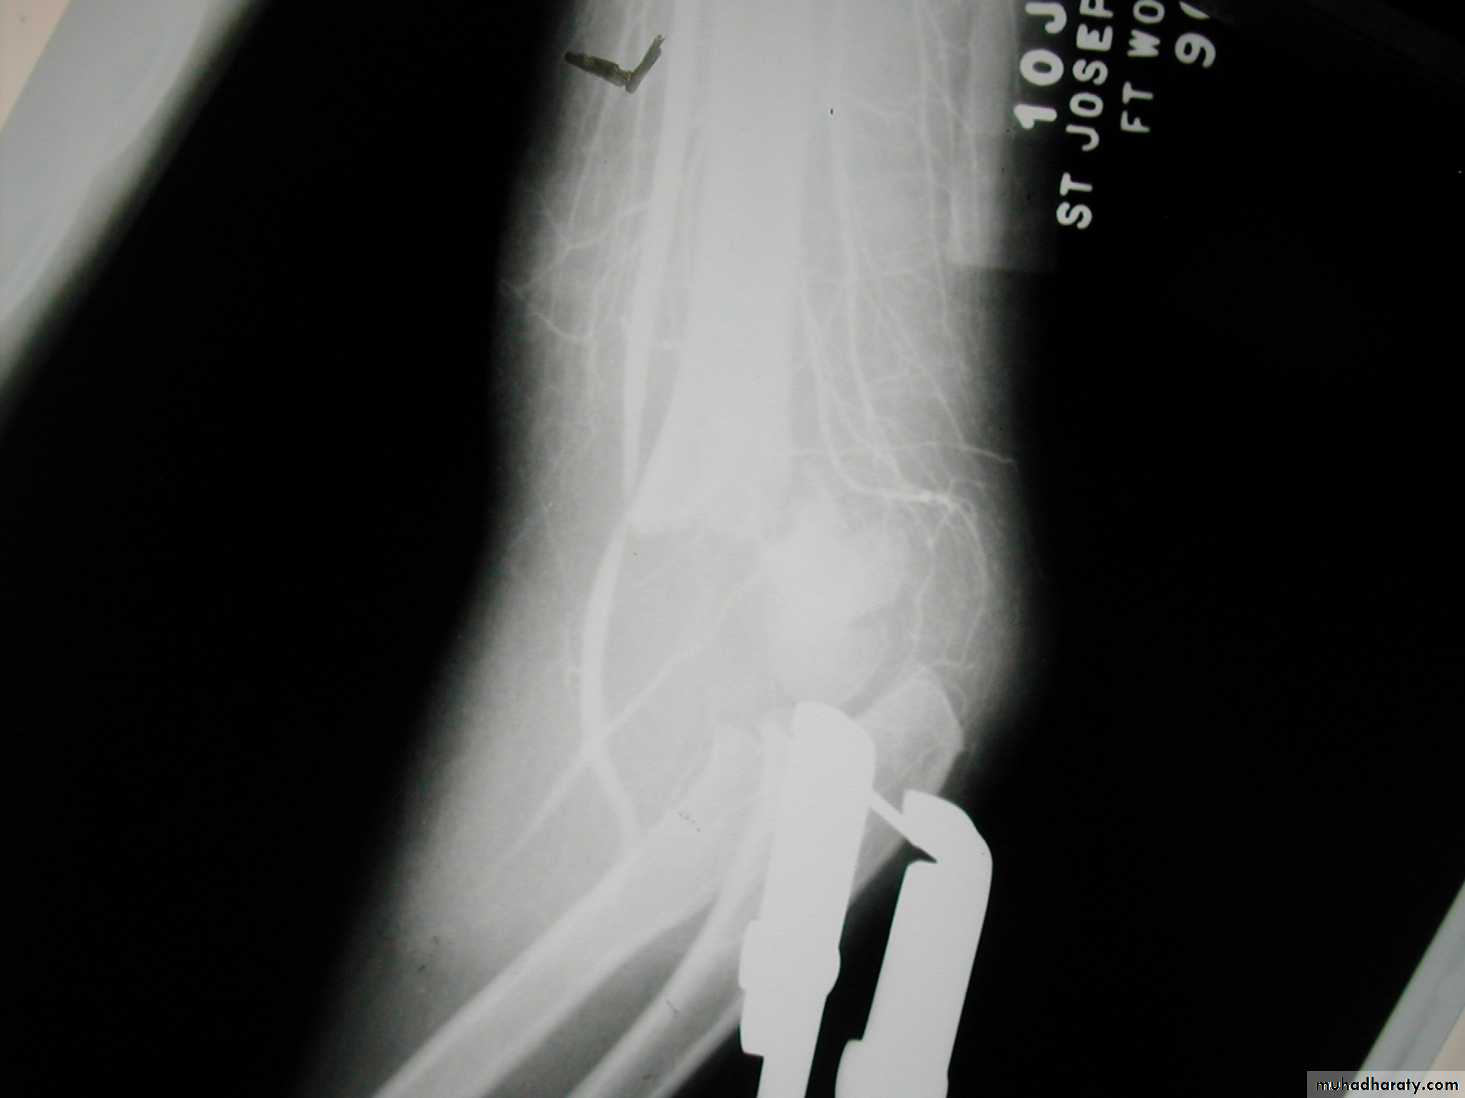

when I was a resident !!6 y.o. sustained this FX. NV intact.

Following obtaining a satisfactory closed reduction how do you propose to stabilize it?• Medial-lateral pins

6 y.o. sustained this FX. NV intact.

Following obtaining a satisfactory closed reduction how do you propose to stabilize it?Multiple lateral pins

Outside fracture line ?6 y.o. sustained this FX. NV intact.

Following obtaining a satisfactory closed reduction how do you propose to stabilize it?